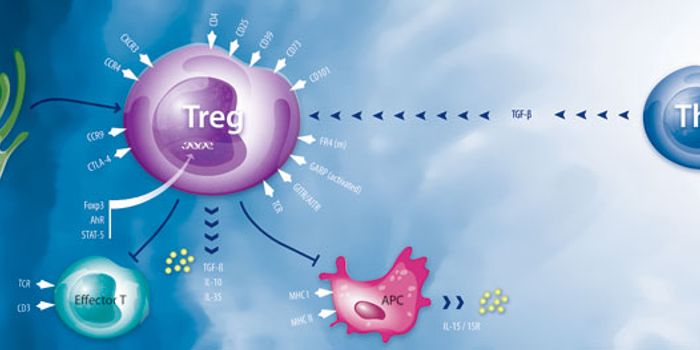

FEB 04, 2016ImmunologyThe body needs regulatory T cells (Tregs) on the sidelines of an immune attack, making sure tempers don’t run too ...